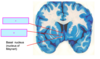

Below is a coronal section of the cerebrum. Which of the following labels corresponds to an intrinsic nuclei of the basal ganglia? A B C D

Below is a coronal section of the cerebrum. Which of the following labels corresponds to an intrinsic nuclei of the basal ganglia? A B **C** D